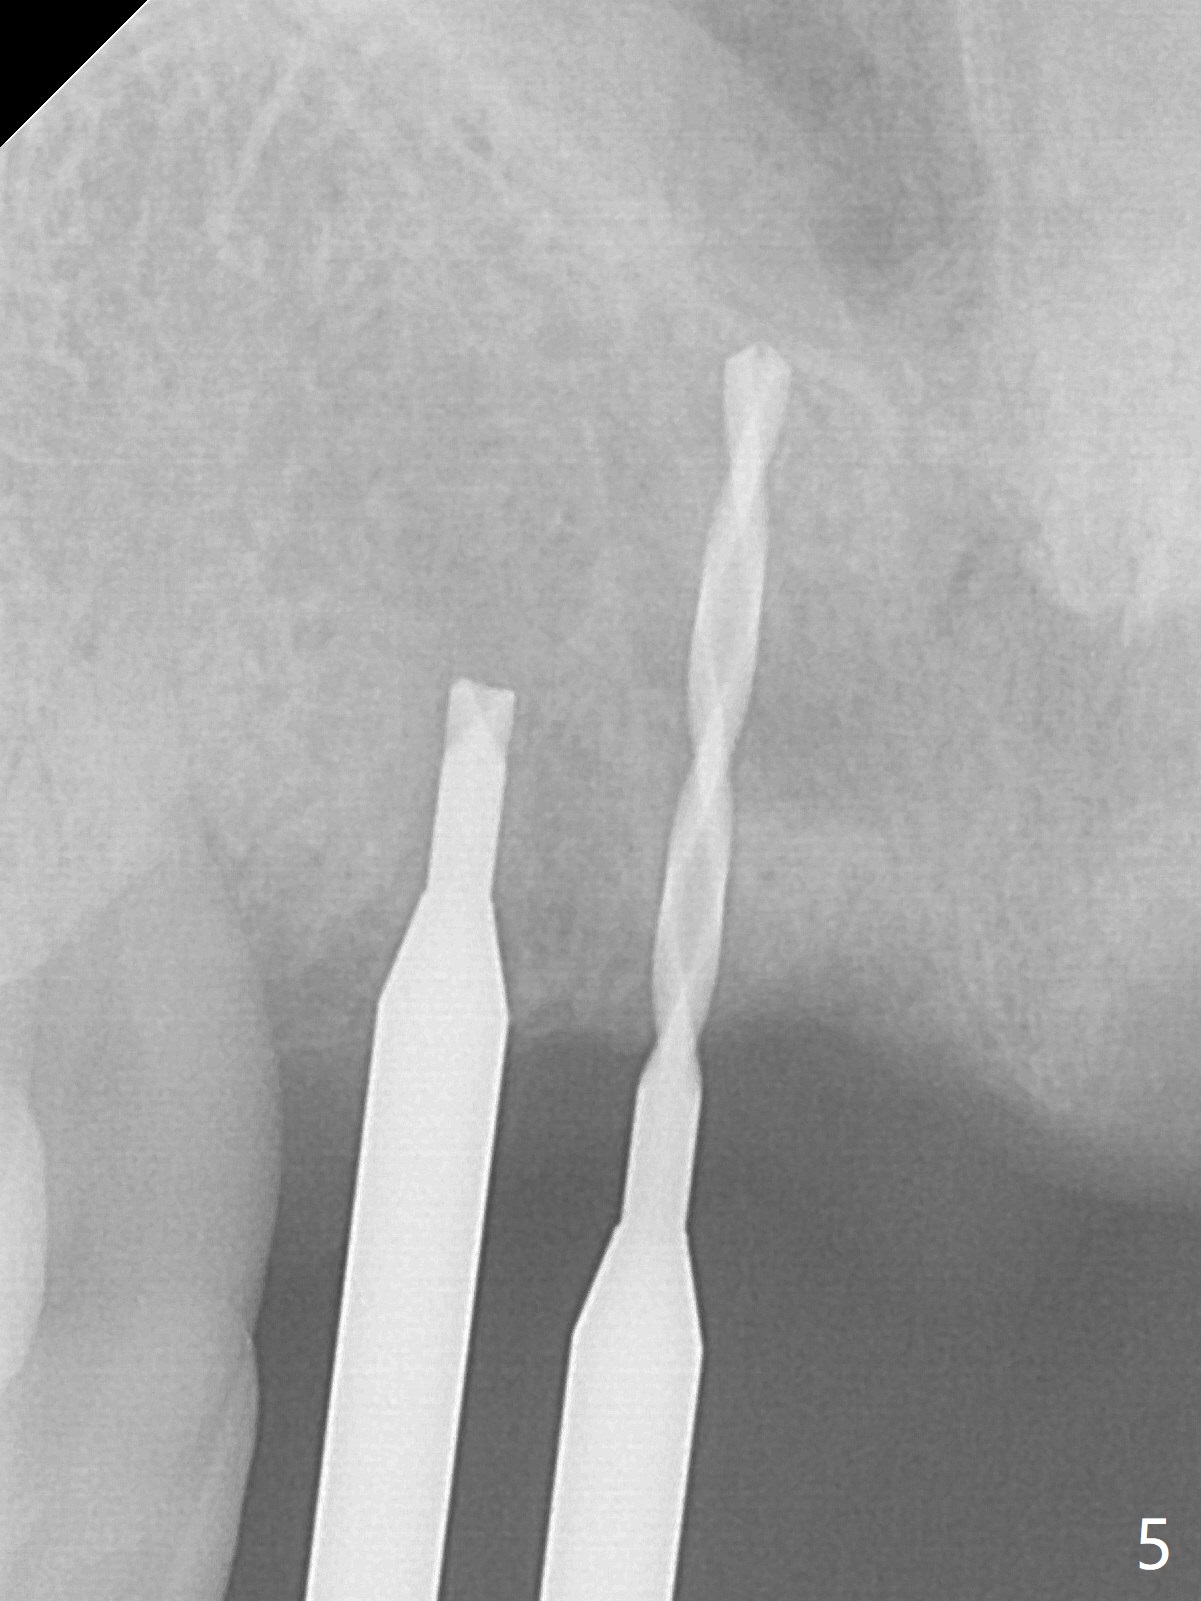

Although the ridge of the maxillary anterior ridge looks moderate in width (Fig.1), the bone is ~4 mm buccopalatally. Suction down surgical stent (Fig.2') made from the lab-fabricated provisional (Fig.2) will be used to check the position and trajectory of osteotomies. PAs taken after initial osteotomies (1.2 mm drill) show those at the central incisors tend to be mesial (close to the Incisive Canal *), while those at the lateral incisor sites distal (Fig.3,4). After adjustment, the position and trajectory of the osteotomies are acceptable (Fig.5,6). To reduce the chance of perforating the Incisive Canal (Fig.3,4 *), 2.5 mm 1-piece implants are inserted with >40 Ncm (Fig.7,8). After deep placement of the implants, Vanilla graft is placed at the crest (Fig.9,10 *). An immediate splinted provisional is fabricated from the suction down stent. The gingiva is healthy around the provisional (Fig.11) and the implants (Fig.12,13) 1 month postop. The provisional is adjusted monthly so that the interdental papillae can be elongated. No bone resorption is observed 6 months postop (Fig.14,15). Crowns are cemented 8 months postop (Fig.16-18). The keratinized gingiva appears to have formed the abutments 8 months postop immediately pre-cementation (Fig.19).